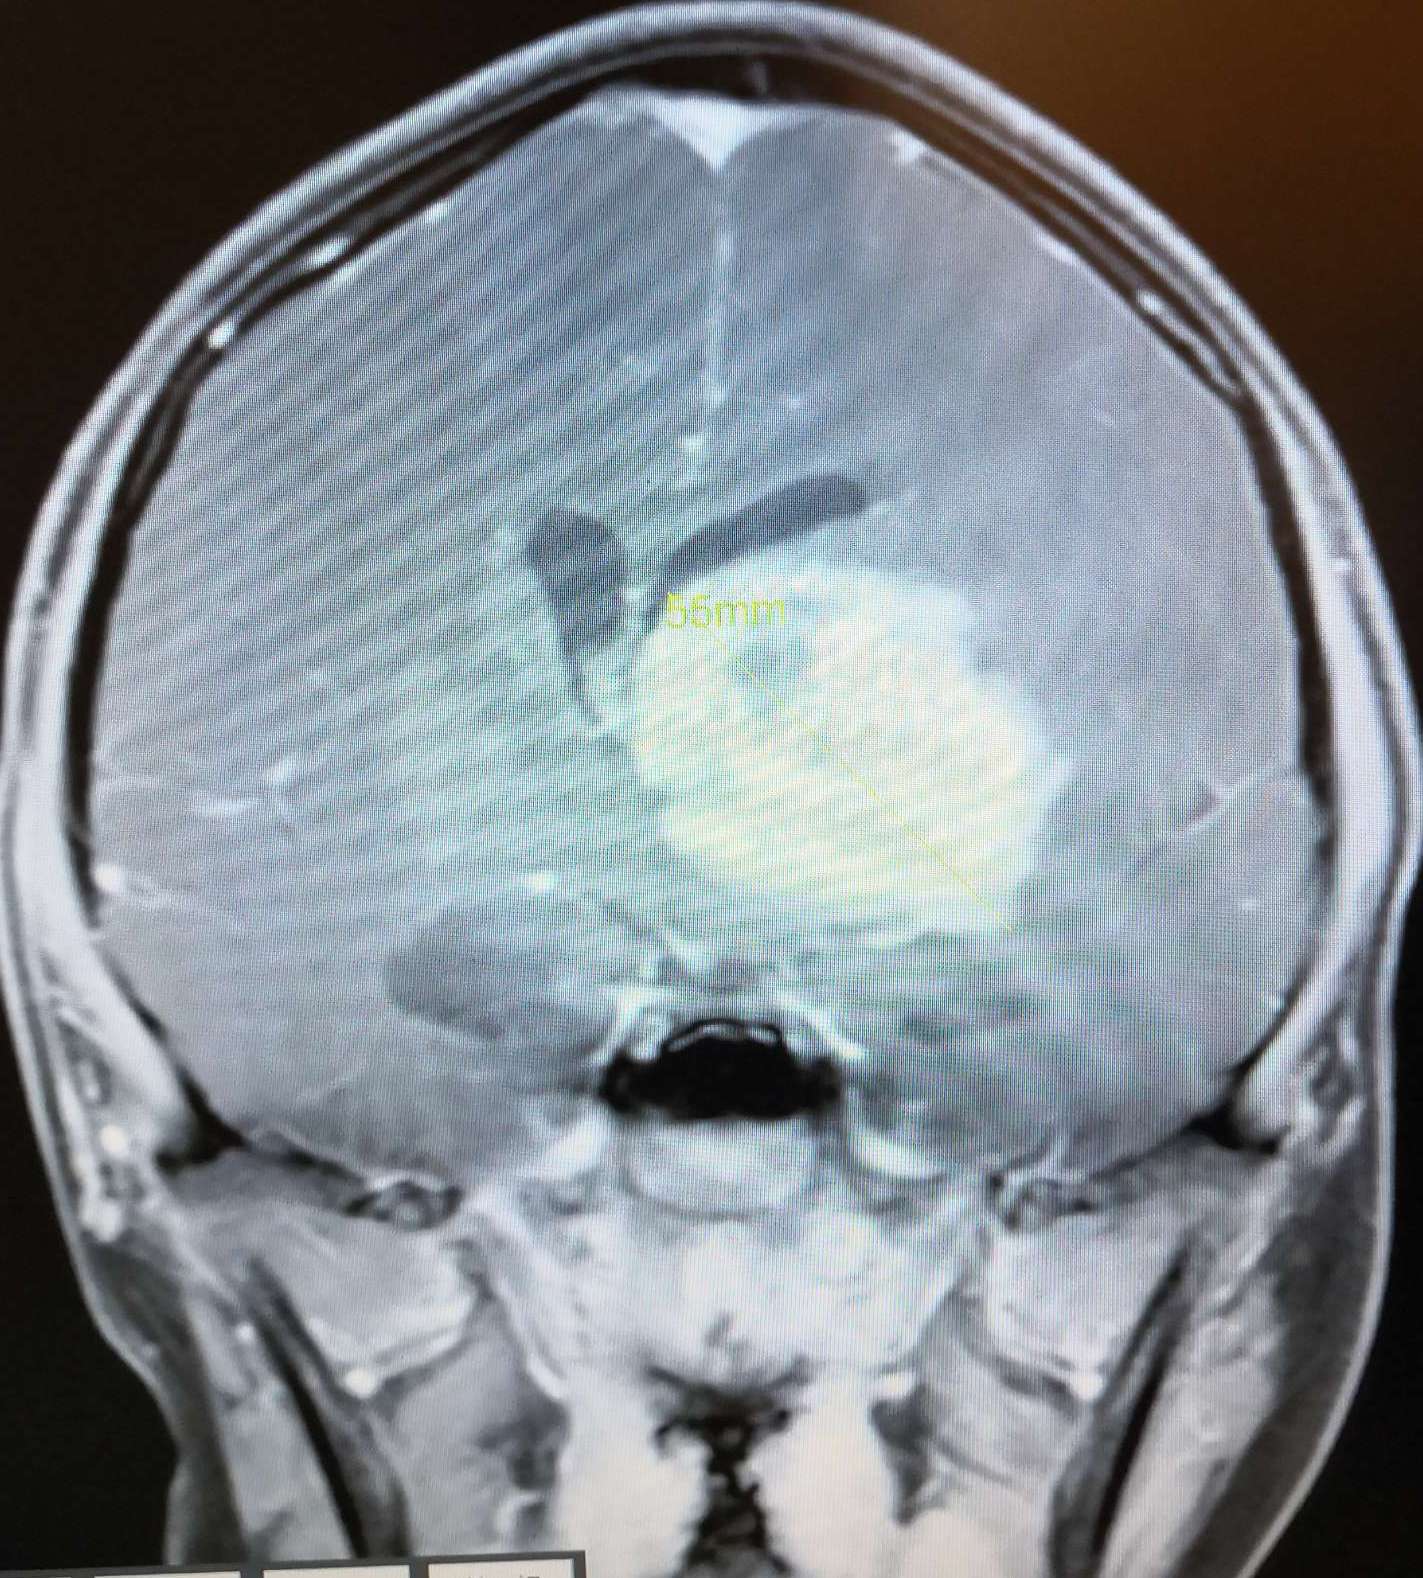

术前头颅MRI增强扫描显示:病灶强化明显,脑室受压,中线移位明显。

术前头颅MRI 增强扫描显示:病灶强化明显,脑室受压。

术前头颅MRI 增强扫描显示:病灶强化明显,脑室受压,中线移位明显。